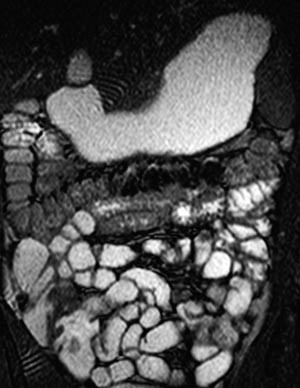

MR av tynntarm med sonde

En viktig forutsetning for radiologisk fremstilling av tynntarmen er at tarmslyngene er utspilt. Hvis tynntarmen har falt sammen, kan patologiske tilstander overses. Én MR-metode innebærer nedleggelse av sonde til tynntarmen og installasjon av væske i denne (1) – (6). Væsken vil vanligvis være tilsatt et stoff som hindrer absorpsjon. Undersøkelsen starter med at pasienten får lagt ned en sonde til proksimale tynntarm på et gjennomlysningslaboratorium. Sonden blir lagt forbi Treitz’ ligament. Den har en ballong distalt som hindrer refluks til ventrikkelen. Deretter fortsetter undersøkelsen på MR-laboratoriet. Pasienten ligger i bukleie i magneten. Sonden kobles til en pose med væske. Væskeinfusjonen starter ved hjelp av manuell installasjon og overvåkes med MR-fluoroskopi (fig 1). Når høyre colonhalvdel er godt væskefylt, stoppes væskeinstallasjonen og man starter de øvrige sekvensene.